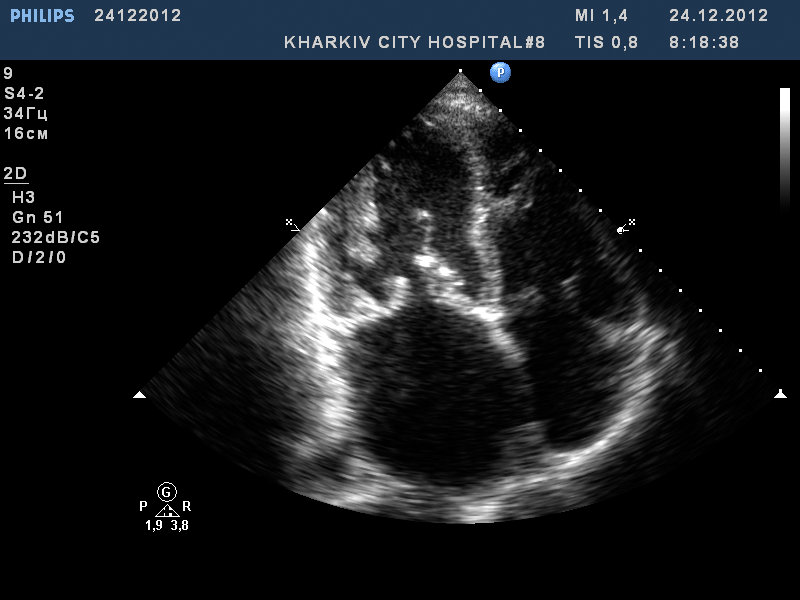

Митральный стеноз, частичный отрыв хорд передней створки МК

Пациент 52 лет. Поступил с нарушение ритма.

Заключение узи : склеротические изменения аорты, фиброзные изменения створок аортального клапана, незначительная недостаточность аортального клапана, частичный отрыв хорд передней створки митрального клапана, значительный митральный стеноз, умеренная МН, дилатация левого предсердия (6,0см), гипертрофия левого желудочка.